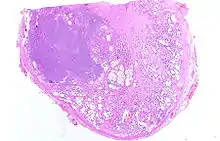

Adénocarcinome prostatique

Adénocarcinome ; tissus indifférenciés

Invasion périneurale par un adénocarcinome prostatique. HE, x400

Anatomopathologie

Le cancer entreprend la portion périphérique de la glande, au contraire de l'hypertrophie prostatique bénigne qui intéresse la zone centrale, périurétrale.

La gravité de l'évolution est corrélée avec l'aspect microscopique (score de Gleason), le niveau de PSA et l'extension de la maladie[53].

Score de Gleason

La structure tissulaire des cancers de la prostate varie des formes différenciées (cellules cancéreuses ressemblant aux cellules saines), dite de grade 1, aux formes les moins différenciées (cellules cancéreuses présentant beaucoup de caractères atypiques par rapport aux cellules saines), dite de grade 5.

Plusieurs grades peuvent se rencontrer au sein d'un même tissu. Le score de Gleason est calculé de la façon suivante : on additionne les deux grades les plus représentés de la tumeur. Le premier chiffre représentant le score du contingent le plus représenté. Ainsi 4+3 est plus péjoratif que 3+4

Si la somme est de 6 ou moins, le cancer est dit bien différencié, donc de meilleur pronostic ; 7 : le cancer est moyennement différencié ; 8 ou plus : le cancer est peu différencié, donc de moins bon pronostic.